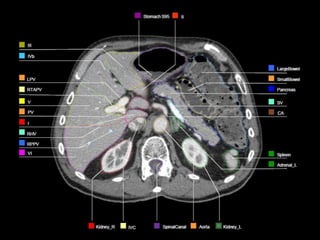

ROI Delineation:Post-op Bed

 Location of tumor should be reviewed and contoured

based on pre-op imaging.

 Surgical clips placed should only be included if there is

documentation from the surgeon intraoperatively such

as close margins or specific tumor related .

ROI Delineation:PJ and HJ

 PJ is identified by following pancreatic remnant medially

and until the junction with the jejunal loop is noted.

 HJ is identified by following air in biliary tree to CHD or

CBD remnant to jejunal loop , or by following PV out of

liver to jejunal loop region.

ROI Delineation:Ao and PV

 Aorta(Ao) extending from top of the upper most PV,CA or

SMA slice to the bottom of L2 or L3.

 Portal vein(PV) is contoured from the bifurcation of the PV .

The PV bifurcation can be extrahepatic or almost

intrahepatic.

(portion of portal vein running anterior and medial to IVC

and stop prior to confluence of SMV or splenic vein).

ROI Delineation:CA and SMA

 Celiac artery (CA): The most proximal 1.0-1.5 cm of the

CA and should include up to the first branching.

 Superior mesenteric artery (SMA): The most proximal

2.5-3.0 cm of SMA.